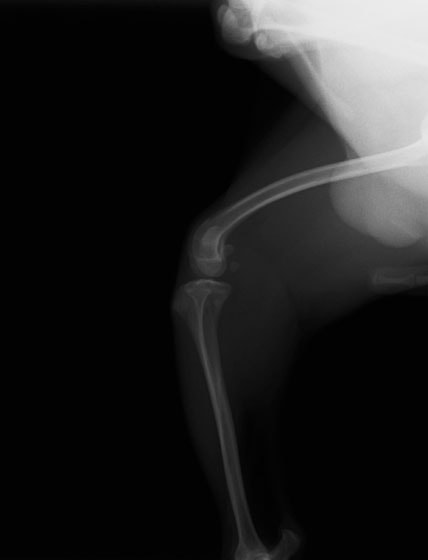

■ 症例20 ポメラニアン 8ヶ月 1.8kg

左右膝蓋骨脱臼 グレードⅢ

2ヶ月前から間欠的跛行が認められ、両膝の膝蓋骨脱臼整復術を行った。

手技は縫工筋及び内側広筋の解放、脛骨粗面の外側転位、滑車ブロック形造溝術、内外側関節包の縫縮を選択し実施した。

右側の膝蓋骨脱臼は上記手技で整復されたものの、左側はそれのみでは膝蓋骨が浮く様子が認められた。その為、PDS縫合糸にて膝蓋靱帯を1糸のみ縫合し、靱帯の縫縮を行った。

膝蓋骨脱臼は膝関節における膝蓋骨の内外側の脱臼と定義されるが、時として単純な内外の脱臼ではなく、膝蓋骨が大きく前方に浮き上がるように脱臼する場合がある。特にトイプードルやポメラニアンといった犬種に多く認められる。

内側脱臼に加えて前方への浮き上がりを矯正する為に、従来より脛骨粗面転移により膝蓋靭帯を外方と下方に引っ張り、固定する方法を選択する。膝蓋骨の前方への浮き上がりが軽度の場合は、従来法ではなく関節包の縫縮で対応していた。しかし、一部の症例で膝蓋骨の動きが悪くなり伸展機構が円滑に機能せずロボット様歩行になるケースがあった。

その為、膝蓋靭帯自体を縫縮する方法を採用した。この方法により、膝関節の伸展機構を妨げず膝蓋骨の軽度の浮きを矯正することが可能となった。

本症例の経過は良好である